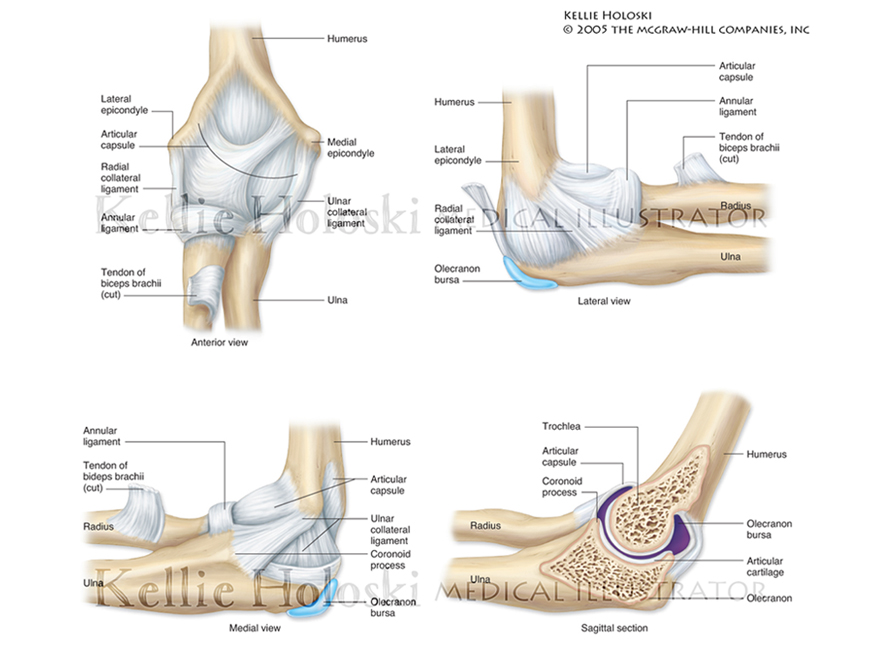

The Elbow Joint,

Adobe Photoshop

Published in Human Anatomy, 1st Edition by Michael McKinley, Valerie O’Loughlin;

©The McGraw-Hill Companies -